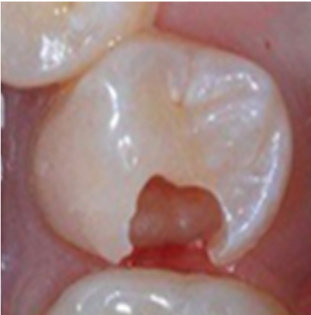

Milk Teeth Filling Results

child-teeth-cavities-beforechild teeth cavities after